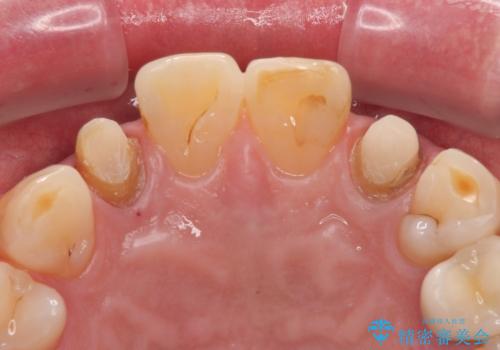

金属の土台を外し、ファイバーコアを築造し、オールセラミッククラウンに適切な形に整えました。

左上の2番目の歯の型どりの段階で患者様より右上の2番目の歯も治療をしてほしいとのことで、根管治療(保険診療)、ファイバーコア、オールセラミッククラウンによる補綴治療を行いました。

歯と歯茎の間に圧排糸と言われる糸を入れてシリコーン印象材にて型どりをしました。